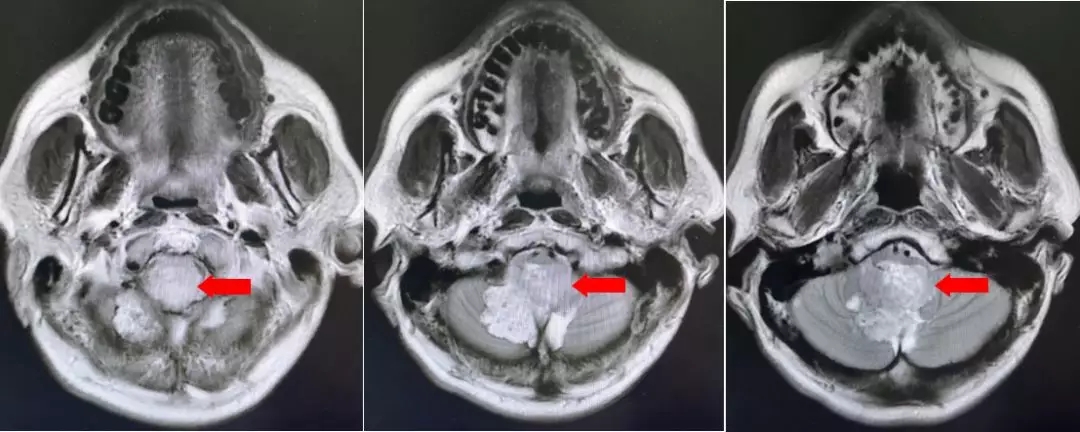

颅脑核磁增强扫描

第四脑室内见一巨大形态不规则的异常信号影,肿瘤信号不均匀,T1W1呈略低信号影,T2W1呈稍高及高信号影,增强扫描可见肿瘤不均匀明显强化。肿瘤充满整个四脑室,大小约44*37*55mm,上方接近四脑室顶部,下方至颈2脊髓平面上方,已经部分侵袭桥脑、延髓,局部边界不清,无明显间隙,脑干局部明显受压变形。肿瘤上方脑室系统扩张,出现梗阻性脑积水征象。

影像诊断:1.第四脑室内占位性病变,室管膜瘤可能性大;2.梗阻性脑积水。